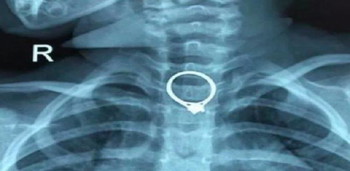

anak tertelan cincin

Screenshot: SOHU News

Ibunya yang risau bergegas membawa anaknya ke Hospital Zhuhai. Doktor di hospital tersebut akhirnya berjaya mengeluarkan cincin berlian berukuran 2.35cm kali 2.04cm, selepas 30 minit pembedahan.